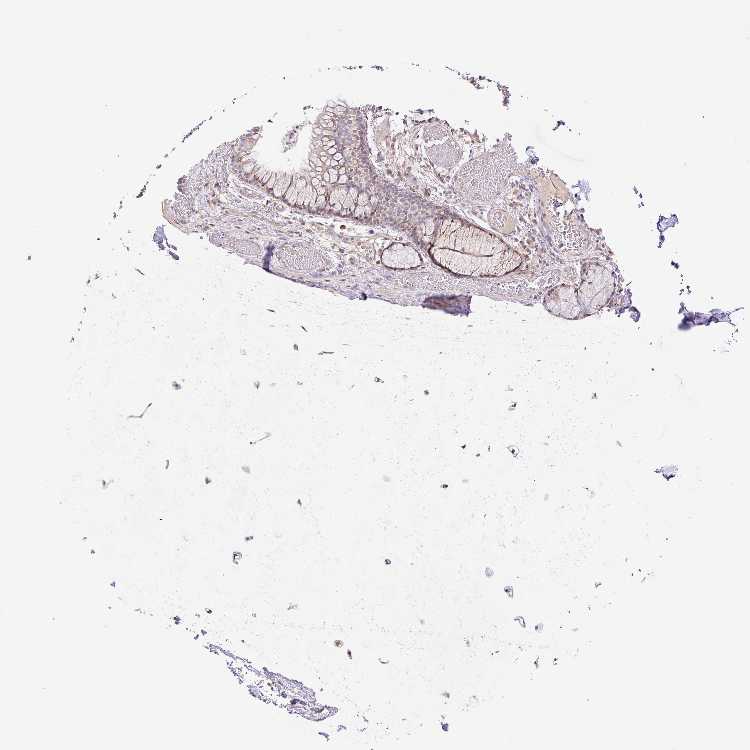

SOFT TISSUE 1 - Antibody stainingi

Antibody staining in the annotated cell types in the current human tissue is reported as not detected, low, medium, or high, based on conventional immunohistochemistry profiling in selected tissues. This score is based on the combination of the staining intensity and fraction of stained cells.

Each image is clickable and will lead to virtual microscopy that enables deeper exploration of all samples and also displays staining intensity scores, fraction scores and subcellular localization as well as patient and tissue information for each sample.

Antibody HPA054519

Chondrocytes Not detected

Fibroblasts Low

Peripheral nerve Not detected

SOFT TISSUE 2 - Antibody stainingi